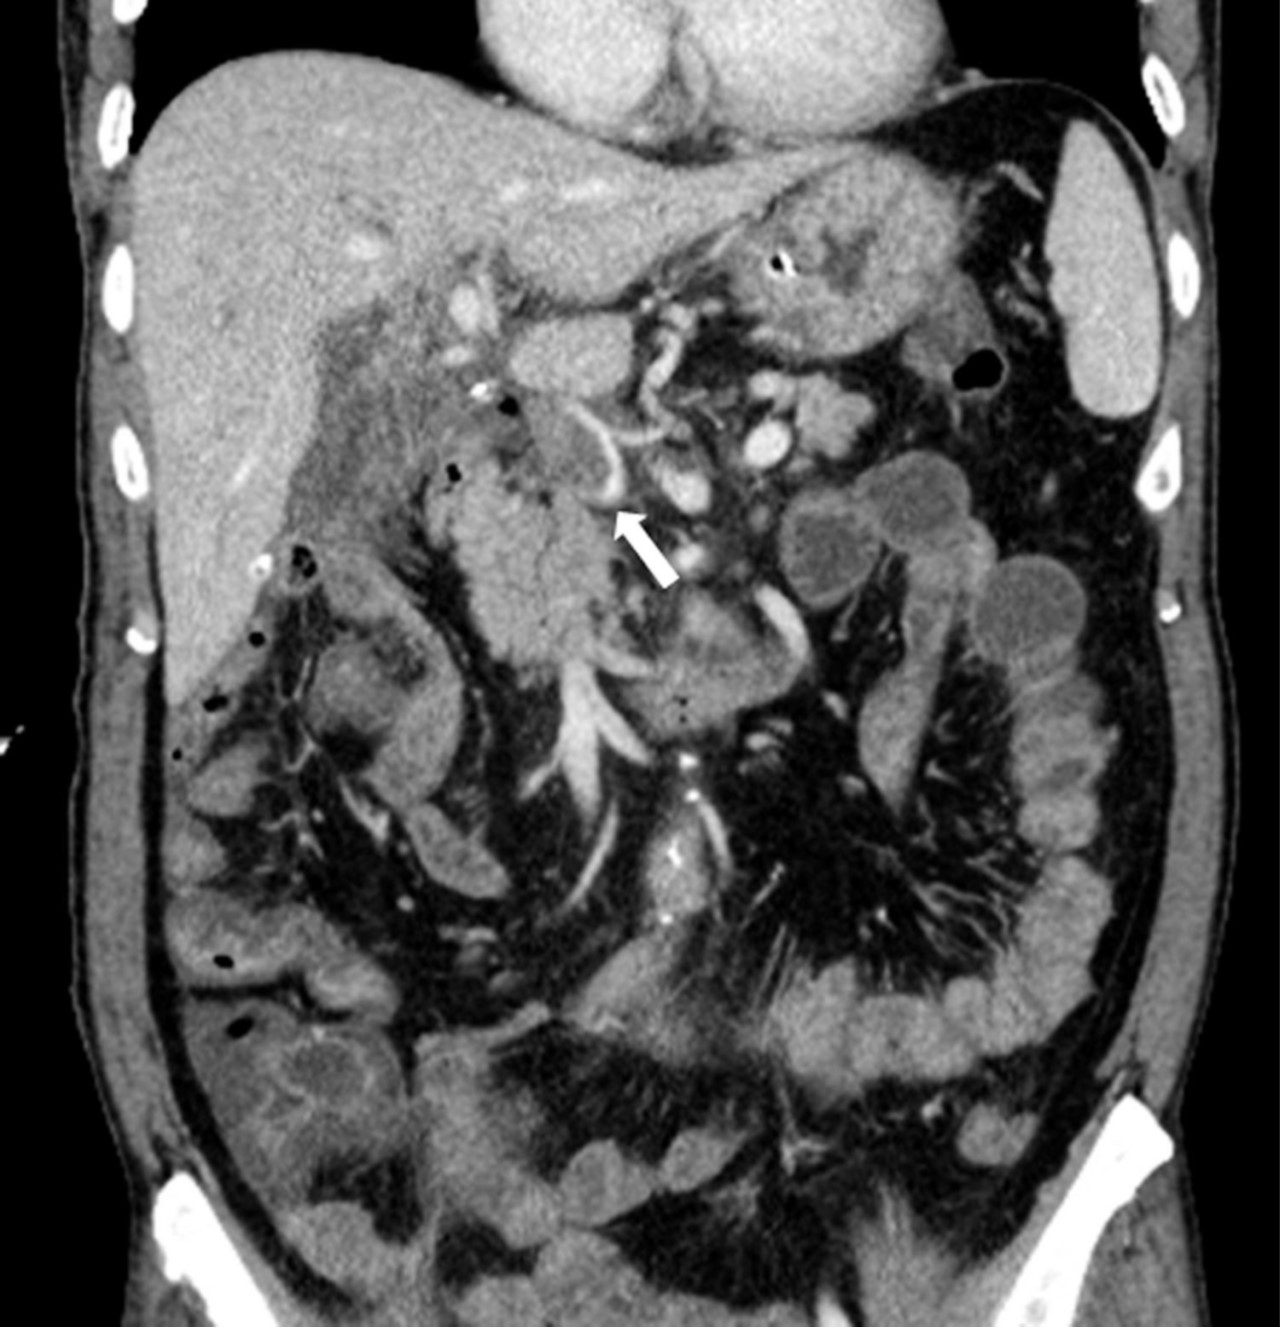

Figure 1. Contrast-enhanced CT scan following segmental resection of bile duct with Roux-en-Y hepaticojejunostomy and segmental resection of portal vein with end-to-end anastomosis. Both axial (A) and coronal (B) studies show a thrombus (arrows) in the narrowed main portal vein and peripheral portal flow is not seen.

총담관과 간문맥 분절 절제 및 루엥Y 간공장문합술 시행 3일 후 촬영한 간 도플러 초음파에서 문맥의 혈류가 관찰되지 않았으며 주문맥을 비롯하여 양측 문맥에 동일에코의 결절들이 있어 혈전증으로 생각되었음. CT에서도 주문맥이 혈전에 의해 폐쇄되어 있어 원위부 문맥 혈류가 보이지 않았음(Fig. 1).